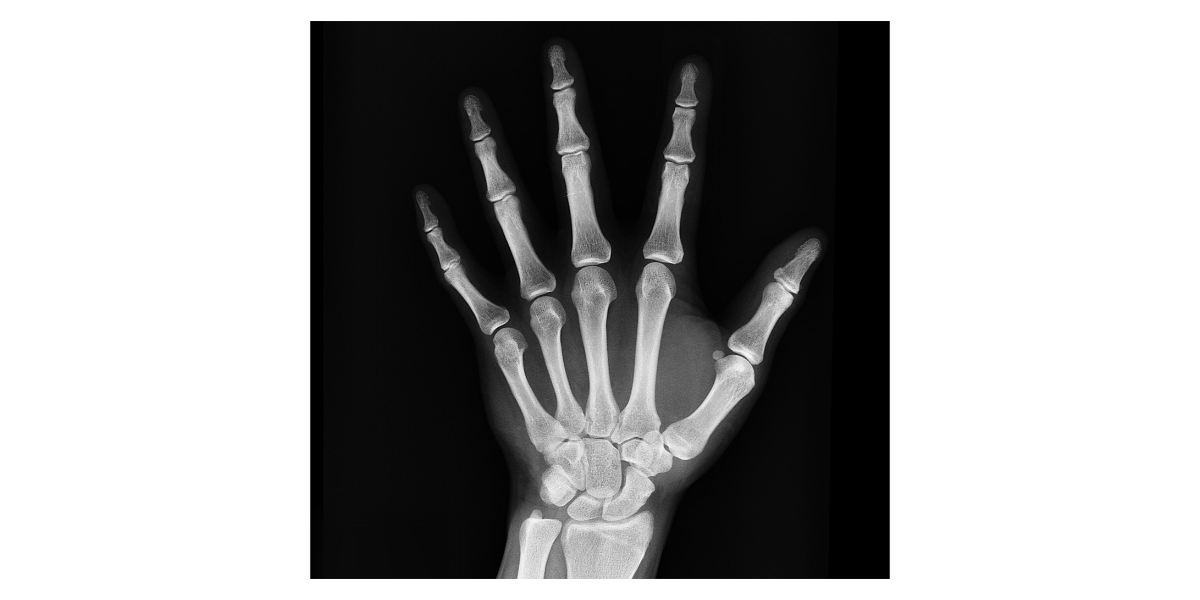

류마티스관절염의 증상은 매우 다양하고, 초기에는 피로감, 미열, 식욕 저하처럼 관절과 직접적으로 관련 없는 증상부터 시작되는 경우가 많습니다. 때문에 일반적인 피로로 오인되거나 다른 질환으로 오해되기 쉬워, 조기 진단이 어렵습니다. 가장 대표적인 증상은 관절의 통증과 뻣뻣함입니다. 특히 아침에 일어났을 때 손가락이나 손목이 굳어 있는 느낌을 받는 경우가 많으며, 이 증상은 대개 30분 이상 지속됩니다. 시간이 지나면서 점차 관절이 붓고, 누르면 통증이 심해지며, 양쪽 관절에 동시에 나타나는 특징도 있습니다. 예를 들어 오른손이 아프면 왼손도 비슷하게 불편해지는 식입니다. 이후 증상이 진행되면 관절 주변의 연골이나 뼈가 손상되며, 외형적으로도 관절이 변형될 수 있습니다. 특히 손가락 관절이 휘거나, 손바닥 쪽으로 기울어지는 등의 변화가 나타나며, 이는 일상생활에 큰 제약을 줍니다. 단추 채우기, 물건 잡기, 글씨 쓰기 등 간단한 일조차 힘들어지는 경우가 많습니다. 더불어 류마티스관절염은 단순히 관절에만 영향을 주는 질환이 아닙니다. 폐, 심장, 신장, 눈, 피부 등 전신에 염증을 유발할 수 있는 전신성 질환입니다. 이로 인해 호흡 곤란, 가슴 통증, 결막염, 피부 결절 등 다양한 합병증이 나타날 수 있습니다. 또한 우울감과 무기력이 함께 동반되는 경우도 많은데, 이는 만성 통증과 장기적인 치료 과정에서 오는 정서적인 부담 때문입니다. 따라서 류마티스관절염은 신체적 치료뿐 아니라 정서적 지지와 관리도 함께 이루어져야 합니다.